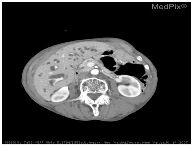

| Image | Category | Generated and Ground Truth Questions |

|---|---|---|

![]() | Plane | what plane is this image obtained? what plane is this image blood-samples? Is this image of a saggital plane? |